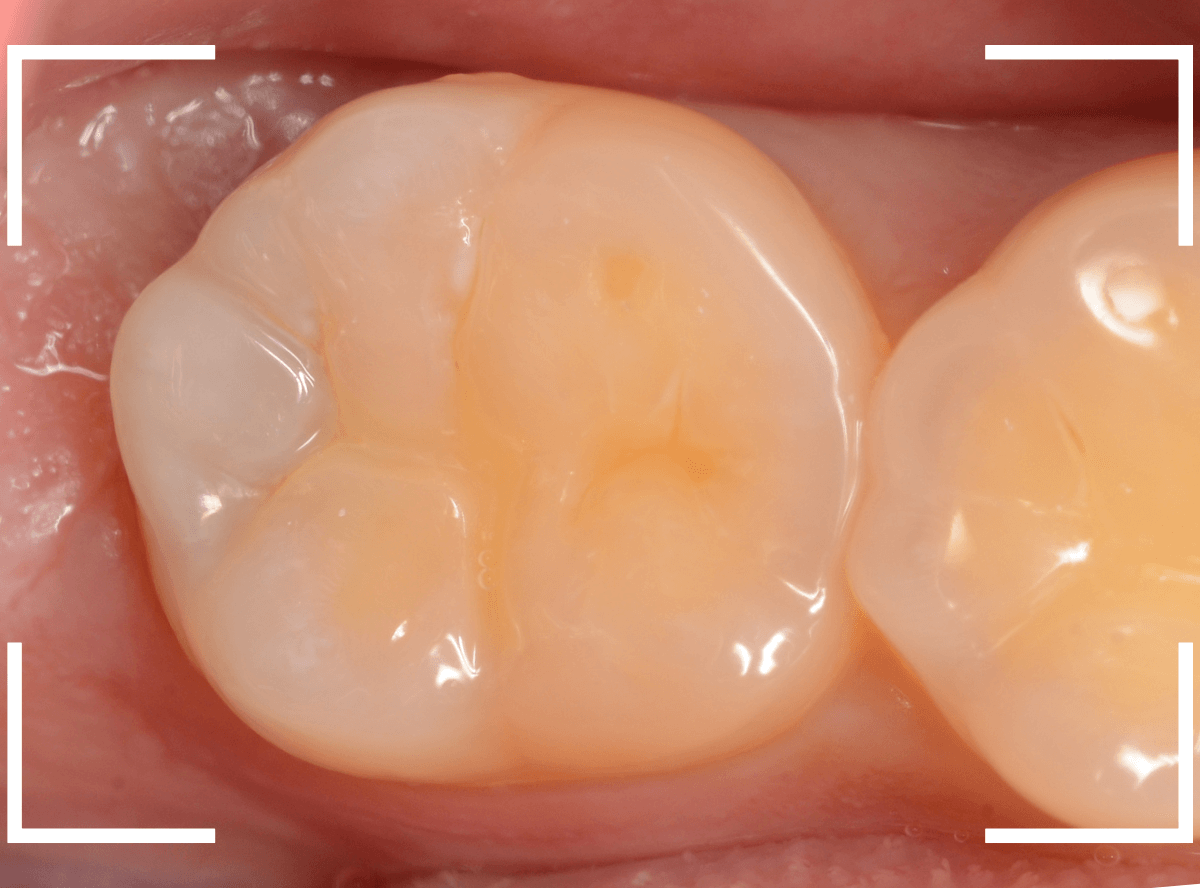

さて、しばらく経過観察した後、症状もありませんでしたので、型どりをして最終修復に入ります。

「良い素材で治療をしたい」という患者さんのご希望でしたので、ジルコニア・インレーで治療をする事になりました。

模型上で精密に製作します。

set後の写真です。

なんとか審美性も確保した状態で治療を終われました。